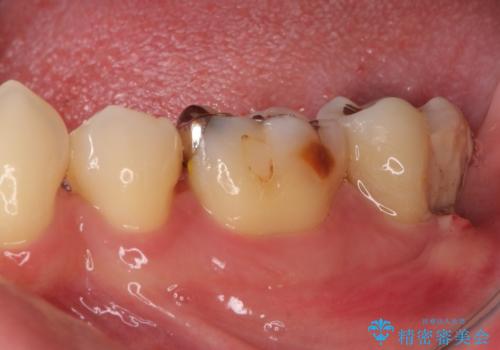

- 左下の奥歯に違和感を感じて来院された患者様です。

診察をした結果、歯根にまで及んだ虫歯と歯周病による著しい骨欠損が認められ、抜歯をせざるを得ない状況でした。